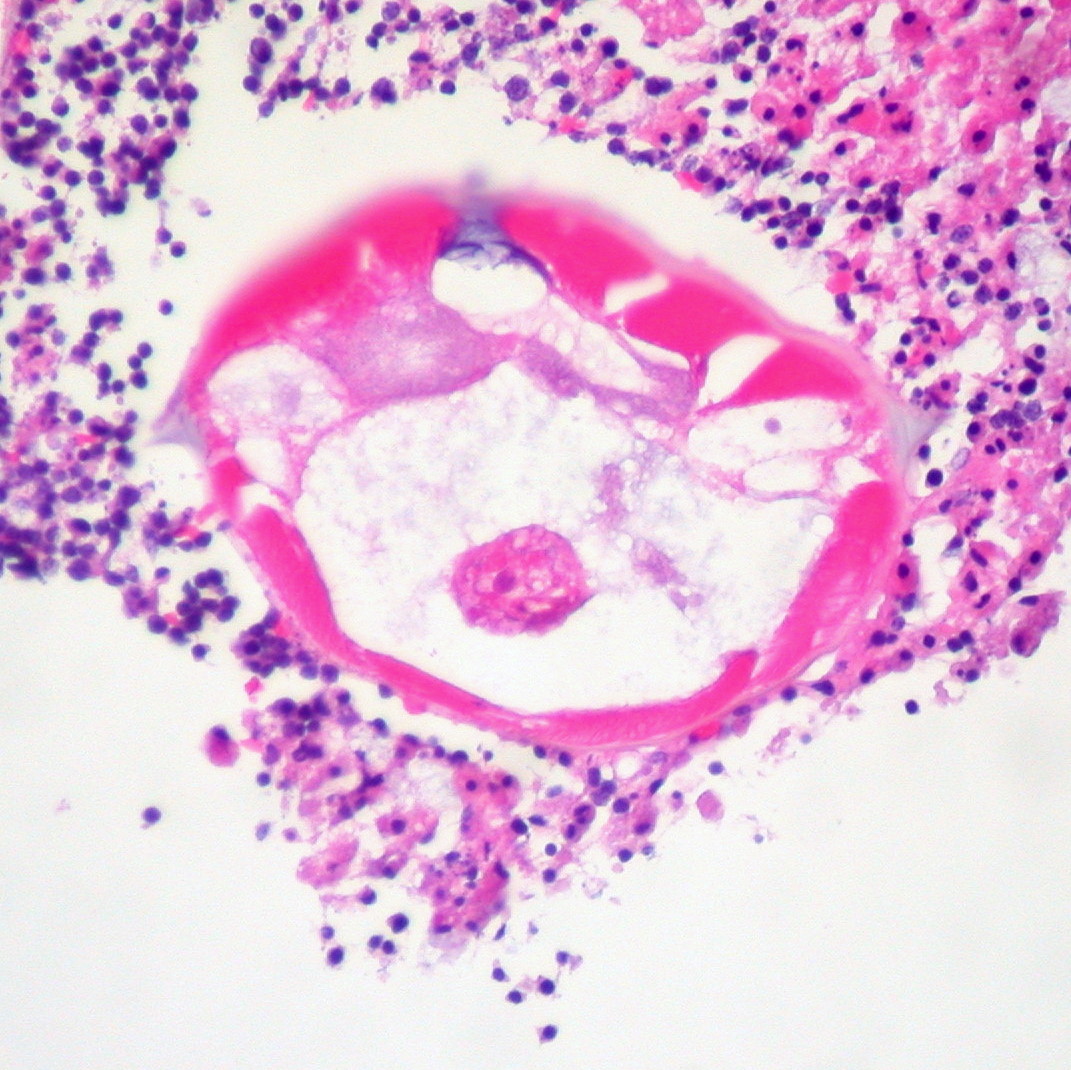

Инвазия острицами диагностируется обнаружением самок гельминта, которые имеют длину около 10 мм (самцы до 3 мм) в перианальной области у детей 1 или 2 лет, когда ребенок идет ложиться спать, или утром, или при обычной световой микроскопии обнаруживаются яйца на липкой пленке. Яйца можно получить утром, когда ребенок встает, путем прижатия специальной ленты к перианальному отверстию, затем прилипающей стороной положить на стекло и посмотреть под микроскопом. Яйца имеют размер 50—30 микрон, овальные, с тонкой оболочкой, внутри находится скрученная личинка. Капля толуола капается между образцом (липкой лентой) и покровным стеклом, растворяет липкую ленту, а также необходимо удалить пузырьки воздуха из-под покрытия, так как они могут помешать идентификации яиц. Если необходимо, эта процедура должна быть повторена до 5 раз для получения успешного результата. Яйца также можно обнаружить, но не часто, в стуле, моче, вагинальном секрете.